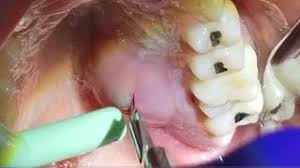

Quick Relief From Gum Pain 7 Home Remedies

Quick Relief From Gum Pain 7 Home Remedies from post.healthline.com